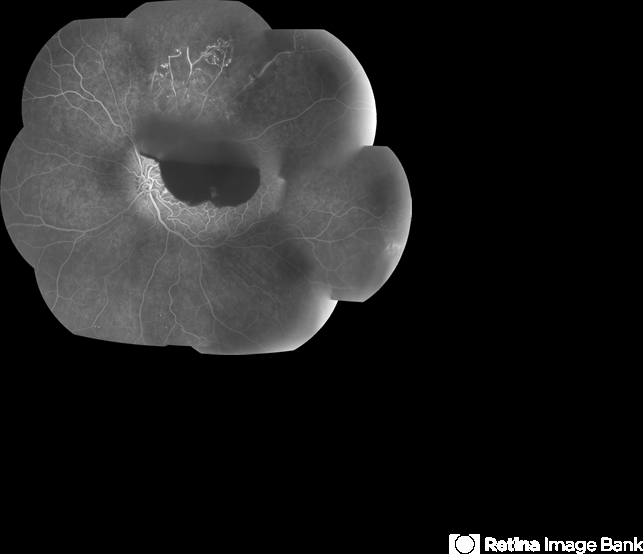

- branch retinal vein occlusion (BRVO), subhyaloid hemorrhage, retinal neovascularization, capillary nonperfusion

- 60-year-old male with a branch retinal vein occlusion and subhyaloid hemorrhage and retinal neovascularization. VA HM.